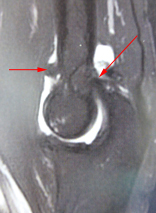

Les radiographies font le diagnostic en montrant un amincissement de l’espace entre les os, des excroissances osseuses appelées “ostéophytes” et des fragments osseux libres dans l’articulation.

L’arthroscanner permet de déceler des atteintes précoces du cartilage et de localiser des petits fragments libres dans l’articulation.

- La mobilité est limitée par des ostéophytes qui peuvent être retirés sous arthroscopie.